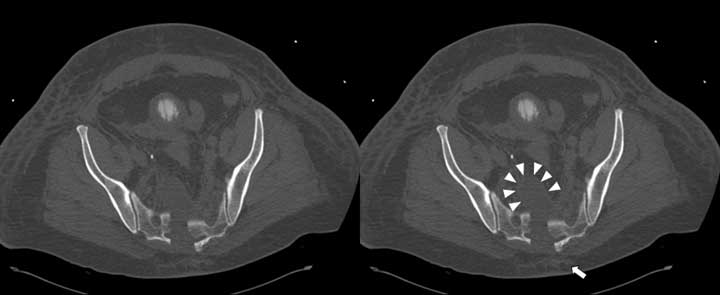

Scans 3D and axial attached (these were done on 17.8.07). I have tried to window the axials to show the nerve roots best.

I am worried that trying to reduce the sacrum might squeeze the nerve roots between fracture surfaces. Even if they don't get pinched I wonder whether the canal should be decompressed from behind with all the oedema around. The possibility of sacral pressure sores in this sick chap over a posterior operation wound is unappealing. Ex-fix would make prone positioning difficult/impossible. These are just a few of the tricky thoughts bothering me about this.